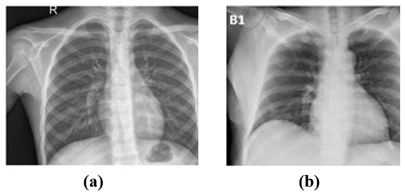

COVID-19 can be detected using real-time polymerase chain reaction (RT-PCR). However, these results take time to verify and are costly. Antibodies that are created as a result of combating the virus can be found in the blood of infected persons. For most people, however, the antibodies do not form until 2 weeks after contracting the virus, making early diagnosis impossible with this test [4]. Medical image processing can address this challenge by improving health care for those who are co-infected with the COVID-19 virus. The medical imaging field relies heavily on X-rays and computed tomography (CT) scans, and several studies have utilized these to create models that can assist radiologists in anticipating illness [6]. Figure 1 shows a negative example with a regular chest X-ray and a positive example with COVID-19.

Figure 1. Samples of chest X-ray images (a) normal and (b) COVID-19